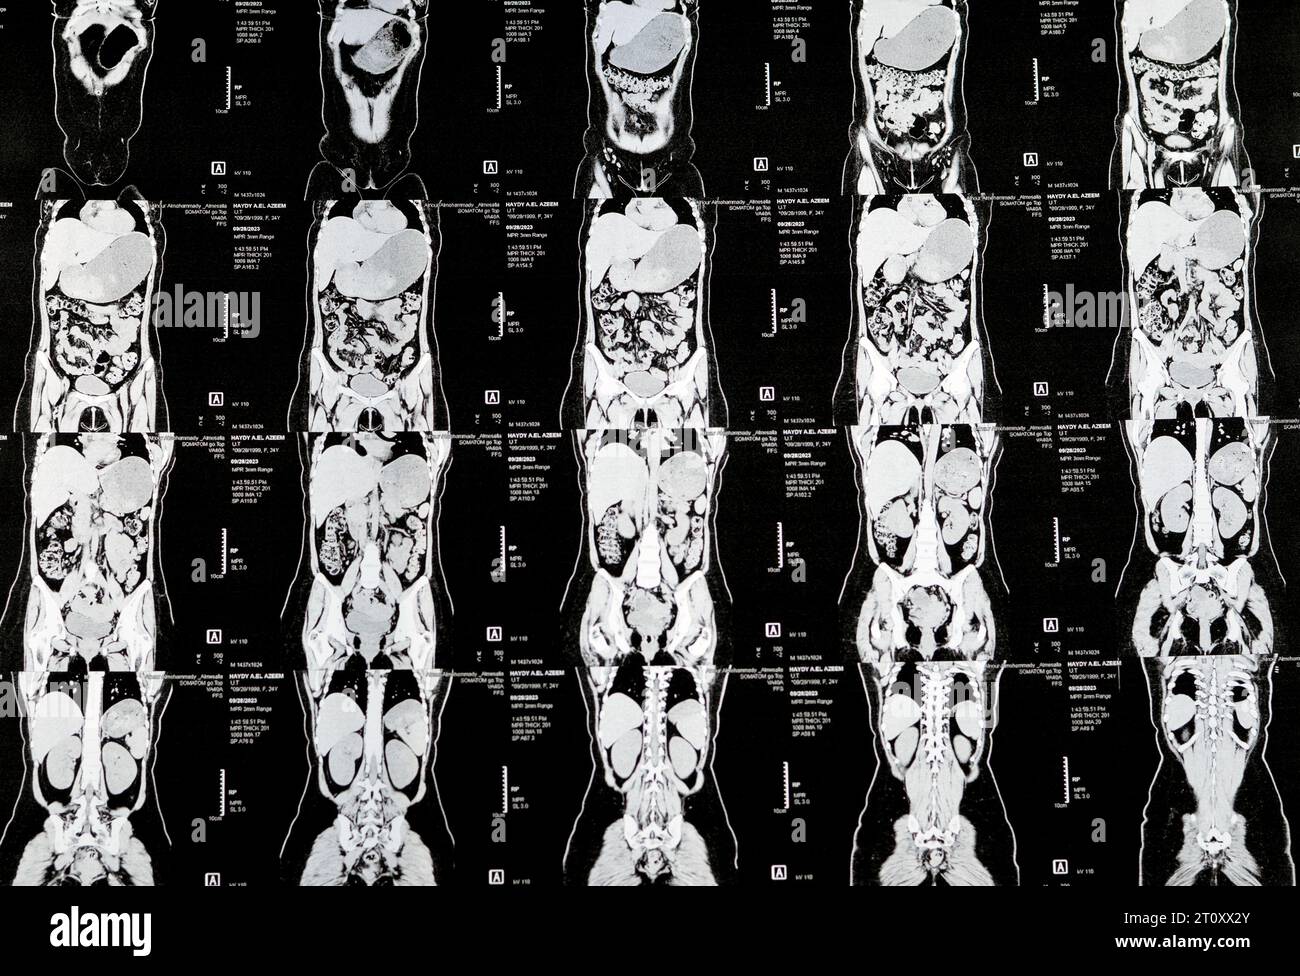

Le Caire, Égypte, octobre 3 2023 : le scanner multi-coupes de l'abdomen et du bassin montre un kyste de l'ovaire droit de 3 x 3 cm, une distension gazeuse colique, pas d'urine importante Banque D'Imageshttps://www.alamyimages.fr/image-license-details/?v=1https://www.alamyimages.fr/le-caire-egypte-octobre-3-2023-le-scanner-multi-coupes-de-l-abdomen-et-du-bassin-montre-un-kyste-de-l-ovaire-droit-de-3-x-3-cm-une-distension-gazeuse-colique-pas-d-urine-importante-image568526222.html

Le Caire, Égypte, octobre 3 2023 : le scanner multi-coupes de l'abdomen et du bassin montre un kyste de l'ovaire droit de 3 x 3 cm, une distension gazeuse colique, pas d'urine importante Banque D'Imageshttps://www.alamyimages.fr/image-license-details/?v=1https://www.alamyimages.fr/le-caire-egypte-octobre-3-2023-le-scanner-multi-coupes-de-l-abdomen-et-du-bassin-montre-un-kyste-de-l-ovaire-droit-de-3-x-3-cm-une-distension-gazeuse-colique-pas-d-urine-importante-image568526222.htmlRF2T0XGYX–Le Caire, Égypte, octobre 3 2023 : le scanner multi-coupes de l'abdomen et du bassin montre un kyste de l'ovaire droit de 3 x 3 cm, une distension gazeuse colique, pas d'urine importante

Le Caire, Égypte, octobre 3 2023 : le scanner multi-coupes de l'abdomen et du bassin montre un kyste de l'ovaire droit de 3 x 3 cm, une distension gazeuse colique, pas d'urine importante Banque D'Imageshttps://www.alamyimages.fr/image-license-details/?v=1https://www.alamyimages.fr/le-caire-egypte-octobre-3-2023-le-scanner-multi-coupes-de-l-abdomen-et-du-bassin-montre-un-kyste-de-l-ovaire-droit-de-3-x-3-cm-une-distension-gazeuse-colique-pas-d-urine-importante-image568533363.html

Le Caire, Égypte, octobre 3 2023 : le scanner multi-coupes de l'abdomen et du bassin montre un kyste de l'ovaire droit de 3 x 3 cm, une distension gazeuse colique, pas d'urine importante Banque D'Imageshttps://www.alamyimages.fr/image-license-details/?v=1https://www.alamyimages.fr/le-caire-egypte-octobre-3-2023-le-scanner-multi-coupes-de-l-abdomen-et-du-bassin-montre-un-kyste-de-l-ovaire-droit-de-3-x-3-cm-une-distension-gazeuse-colique-pas-d-urine-importante-image568533363.htmlRF2T0XX2Y–Le Caire, Égypte, octobre 3 2023 : le scanner multi-coupes de l'abdomen et du bassin montre un kyste de l'ovaire droit de 3 x 3 cm, une distension gazeuse colique, pas d'urine importante

Le Caire, Égypte, octobre 3 2023 : le scanner multi-coupes de l'abdomen et du bassin montre un kyste de l'ovaire droit de 3 x 3 cm, une distension gazeuse colique, pas d'urine importante Banque D'Imageshttps://www.alamyimages.fr/image-license-details/?v=1https://www.alamyimages.fr/le-caire-egypte-octobre-3-2023-le-scanner-multi-coupes-de-l-abdomen-et-du-bassin-montre-un-kyste-de-l-ovaire-droit-de-3-x-3-cm-une-distension-gazeuse-colique-pas-d-urine-importante-image568532396.html

Le Caire, Égypte, octobre 3 2023 : le scanner multi-coupes de l'abdomen et du bassin montre un kyste de l'ovaire droit de 3 x 3 cm, une distension gazeuse colique, pas d'urine importante Banque D'Imageshttps://www.alamyimages.fr/image-license-details/?v=1https://www.alamyimages.fr/le-caire-egypte-octobre-3-2023-le-scanner-multi-coupes-de-l-abdomen-et-du-bassin-montre-un-kyste-de-l-ovaire-droit-de-3-x-3-cm-une-distension-gazeuse-colique-pas-d-urine-importante-image568532396.htmlRF2T0XTTC–Le Caire, Égypte, octobre 3 2023 : le scanner multi-coupes de l'abdomen et du bassin montre un kyste de l'ovaire droit de 3 x 3 cm, une distension gazeuse colique, pas d'urine importante

Le Caire, Égypte, octobre 3 2023 : le scanner multi-coupes de l'abdomen et du bassin montre un kyste de l'ovaire droit de 3 x 3 cm, une distension gazeuse colique, pas d'urine importante Banque D'Imageshttps://www.alamyimages.fr/image-license-details/?v=1https://www.alamyimages.fr/le-caire-egypte-octobre-3-2023-le-scanner-multi-coupes-de-l-abdomen-et-du-bassin-montre-un-kyste-de-l-ovaire-droit-de-3-x-3-cm-une-distension-gazeuse-colique-pas-d-urine-importante-image568507925.html

Le Caire, Égypte, octobre 3 2023 : le scanner multi-coupes de l'abdomen et du bassin montre un kyste de l'ovaire droit de 3 x 3 cm, une distension gazeuse colique, pas d'urine importante Banque D'Imageshttps://www.alamyimages.fr/image-license-details/?v=1https://www.alamyimages.fr/le-caire-egypte-octobre-3-2023-le-scanner-multi-coupes-de-l-abdomen-et-du-bassin-montre-un-kyste-de-l-ovaire-droit-de-3-x-3-cm-une-distension-gazeuse-colique-pas-d-urine-importante-image568507925.htmlRF2T0WNJD–Le Caire, Égypte, octobre 3 2023 : le scanner multi-coupes de l'abdomen et du bassin montre un kyste de l'ovaire droit de 3 x 3 cm, une distension gazeuse colique, pas d'urine importante